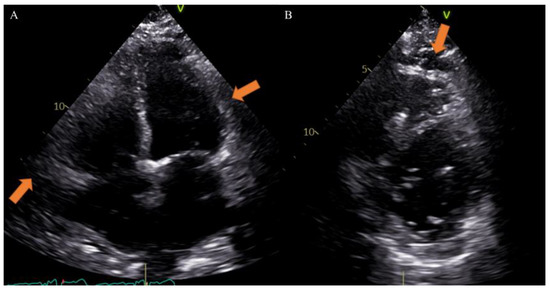

Different imaging techniques can study EAT and include echocardiography, cardiac magnetic resonance (CMR) and computed tomography (CT). Echocardiography is very useful to provide maximum thickness and provides a simple and easily accessible tool for EAT measurement, although it may not reflect the absolute amount of epicardial fat and gives less accurate results due to uneven distribution of epicardial fat and poor acoustic window [33]. Previous studies, however, have reported that echocardiographic measurement closely correlates with the total volume of EAT on other radiologic modalities and considering the great diffusion of this method in clinical practice, it could be very simple to obtain data on EAT [34] (Figure 2).

Figure 2.

Case of a 65-year-old male patient underwent to echocardiography showing epicardial fat tissue on four chambers ((A), arrow) and short axis ((B), arrow) views. From Giuseppe Muscogiuri’s private archive of unpublished cardiac imaging.